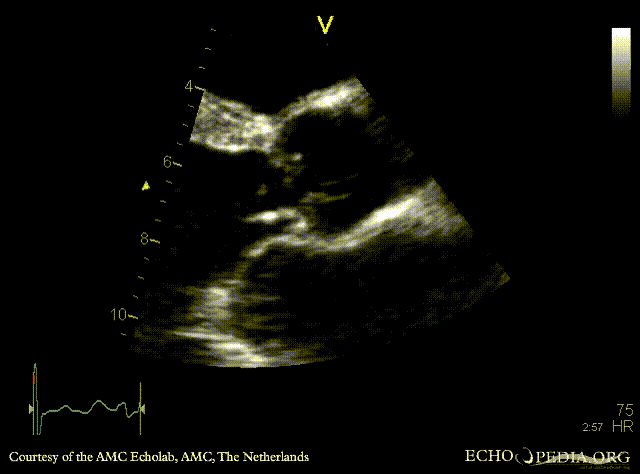

Severe aortic regurgitation

PLAX: aortic valve vegetation, dilated left ventricle PLAX: aortic valve vegetation